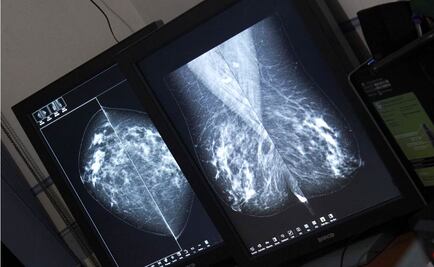

Alcaldía MH y asociaciones civiles donan 100 mastografías para detección temprana del cáncer de mama

En la inauguración de la Expo Salud, Mikel Arriola informó que con la compra de nuevos mastrógrafos durante 2017 aumentará 60% la capacidad de diagnóstico para el siguiente año

El secretario de Salud señaló que es necesario que se abran centros de interpretación de mamografías